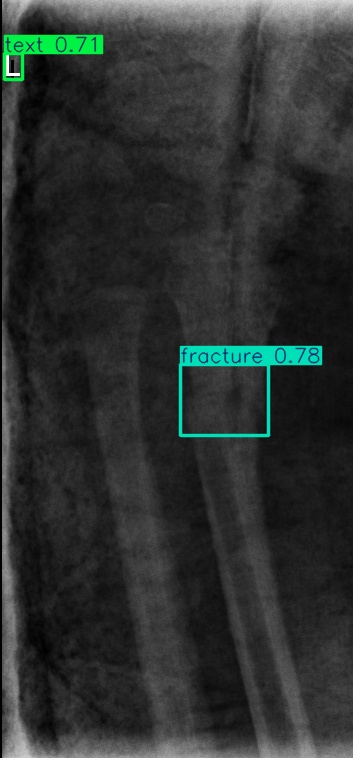

Figure 8: Sample of five images from the GRAZPEDWRI-DX test set, displaying ground-truth and predicted bounding box annotations: (a-e): ground-truth annotations, (f-j): YOLOv11l annotations, and (k-o): G-YOLOv11 annotations.

Table 4: Confidence scores predicted by YOLOv11l and the proposed G-YOLOv11l detectors for five images from the GRAZPEDWRI-DX test set, PR: pronator sign, FP: False positive.

Figure number Class name Confidence score predicted Confidence score predicted

by YOLOv11l by our G-YOLOv11l

8(a) soft tissue, fracture, metal, text -, 0.670.67, 0.860.86, 0.830.83 -, 0.700.70, 0.890.89, 0.840.84

8(b) fracture, text 0.780.78, 0.710.71 0.790.79, 0.730.73

8(c) fracture, text 0.820.82, 0.780.78 0.810.81, 0.790.79, (FP: pr 0.44)0.44)

8(d) fracture, fracture, text 0.770.77, 0.700.70, 0.880.88 0.760.76, 0.520.52, 0.890.89

8(e) fracture, periosteal reaction, text 0.760.76, 0.690.69, 0.760.76 0.750.75, 0.600.60, 0.760.76

The results in Table 4, derived from Figure 8, compares the confidence scores predicted by YOLOv11l and G-YOLOv11l detectors for five test images from the GRAZPEDWRI-DX dataset. Figure 8 contrasts ground-truth annotations with predictions from YOLOv11l and G-YOLOv11l. G-YOLOv11l shows slight improvements, such as higher confidence scores for "fracture" and "metal" in Figure 8(a) (0.700.70 and 0.890.89 vs. 0.670.67 and 0.860.86) and for "text" in Figure 8(b) (0.730.73 vs. 0.710.71). However, limitations include false positives, such as for "pronator sign" in Figure 8(c) (score 0.440.44), and lower confidence for some instances, as seen in Figures 8(d) and 8(e). While G-YOLOv11l demonstrates competitive performance, further refinements are required to improve its robustness.